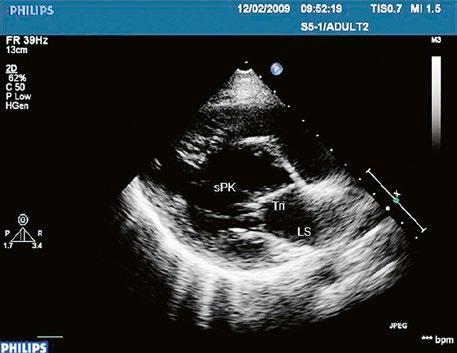

z Defekt síňového septa typu secundum: 70 % všech komunikací na úrovni síní, v místě fossa ovalis, s možnou extenzí ke stěnám levé síně (Obr. 45.1, Obr. 45.2, Video 45.1, Video 45.2).

z Defekt síňového septa typu sinus venosus superior: 9 %, v místě vústění horní duté žíly (HDŽ), která na defekt nasedá, téměř vždy je spojen s parciálním anomálním návratem pravostranných plicních žil do HDŽ nebo do pravé síně (kap. 45.18 Anomální návrat plicních žil (Obr. 45.3, Obr. 45.4, Video 45.3, Video 45.4).

Obr. 45.1 Defekt septa síní typu II v TEE

AO – aorta, DDŽ – ústí dolní duté žíly do pravé síně, defekt septa síní je označen křížky, má předozadní průměr 22 mm, zasahuje blízko zadní stěny levé síně, LS – levá síň, PS – pravá síň

Obr. 45.2 Defekt septa síní typu II v TEE

AO – aorta, ASD – defekt septa síní typu secundum označen šipkou, zelenými křížky je označen malý přední rim k aortě, LS – levá síň, PS – pravá síň